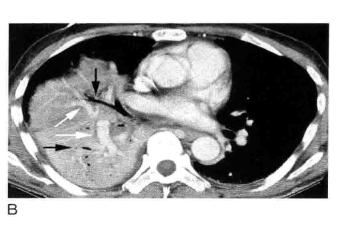

图2 实变:边界不清的,毛玻璃样致密影伴“肺泡充气征”

A. 放大影像细节观察右肺下叶实变呈磨玻璃样边界不清的致密影,内含有小圆形透亮影,称为肺泡充气征,尽管与实际肺泡大小并不相符;B. 右下叶肺炎患者胸部CT显示边界不清的磨玻璃样实变(白色箭头),实变区内小的局灶性透亮影(黑色箭头)为“肺泡充气征”。

3. 肺泡充气征

如果肺实变不融合,可以看到间杂小的局灶性透亮区,代表未受累的肺组织(图2),这些透亮区被称为“肺泡充气征”,但因为肺泡太小无法在X线片上看到,这是一个误称。这些透亮区反映了不完全肺实变。